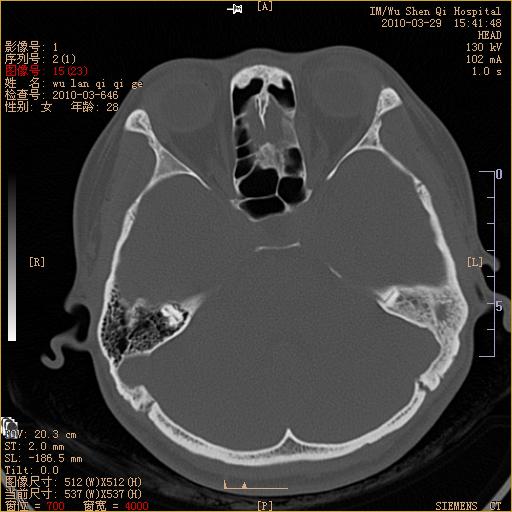

标题: CT25398:女,左耳流脓两年余,带有异物 [打印本页]

标题: CT25398:女,左耳流脓两年余,带有异物

左侧中耳乳突炎,不排除胆脂瘤形成。

左侧中耳乳突炎,胆脂瘤形成。

1)左侧慢性中耳乳突炎并肉芽肿(或胆脂瘤)形成。2)考虑左侧颞骨慢性炎症伴骨质增生硬化,不排除骨纤。